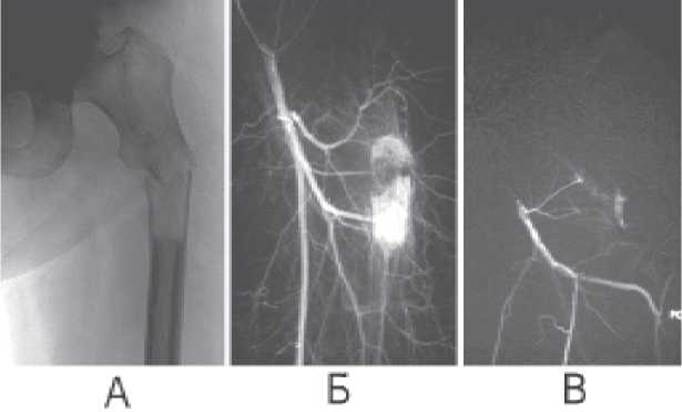

Мал. 27. Ендоваскулярне втручання (емболізація) на серії рентгенограм. А - на рентгенограмі виявляється пухлина, що руйнує губчасту та кіркову речовину стегнової кістки та патологічний перелом проксимальної третини діафіза стегнової кістки; Б - на ангограмі виявляється кровотеча з глибокої Артерії стегна; В - емболізація пошкодженої судини зупиняє кровотечу.